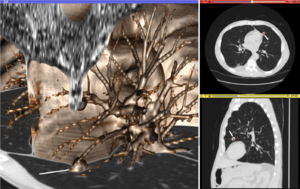

Volume rendering (left), axial cross-section (right top), and sagittal cross-section (right bottom) of a CT image of a subject with multiple nodular lesions (white line) in the lung.

Visualization plays several key roles in Medical Image Computing. Methods from scientific visualization are used to understand and communicate about medical images, which are inherently spatial-temporal. Data visualization and data analysis are used on unstructured data forms, for example when evaluating statistical measures derived during algorithmic processing. Direct interaction with data, a key feature of the visualization process, is used to perform visual queries about data, annotate images, guide segmentation and registration processes, and control the visual representation of data (by controlling lighting rendering properties and viewing parameters). Visualization is used both for initial exploration and for conveying intermediate and final results of analyses.

The figure "Visualization of Medical Imaging" illustrates several types of visualization: 1. the display of cross-sections as gray scale images; 2. reformatted views of gray scale images (the sagittal view in this example has a different orientation than the original direction of the image acquisition; and 3. A 3D volume rendering of the same data. The nodular lesion is clearly visible in the different presentations and has been annotated with a white line.